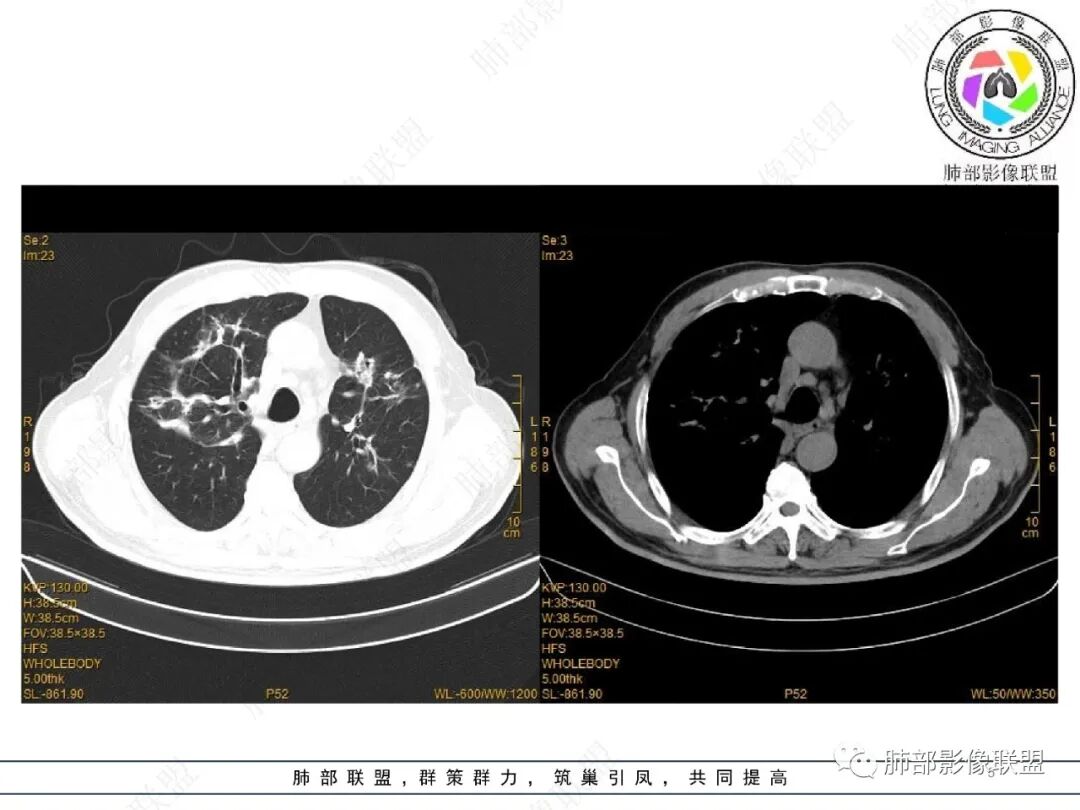

2022.2.17CT显示两肺中内带多发结节影、斑片影、条索影,部分病灶侧向融合与胸膜平行。部分病灶沿着支气管血管束分布、其内支气管稍扩张。部分病灶呈反晕征。大部分病灶边界显示清晰,部分病灶周围可见边界不清的GGO。2022.4.12CT显示两肺中内带多发结节影、条索状、条带状高密度影,边界收缩平直凹陷,大部分病灶沿着支气管血管束分布,亦有位于胸膜下侧向融合与胸膜平行的病灶。总体与第一次CT对比两肺病灶明显吸收。

老年男性,两肺多发病灶,整体呈OP样改变,至于是原发性还是继发性的OP,需要临床鉴别。此病例穿刺结果是隐球菌。该病例CT上缺乏隐球菌典型的“在那遥远的胸膜下,多个蘑菇兄弟,可以侧向融合呈长串状与胸膜平行”影像表现,更多是OP样改变,仅凭临床表现或影像资料诊断隐球菌难度比较大。当然也不除外二元论,导致隐球菌的影像表现被掩盖。